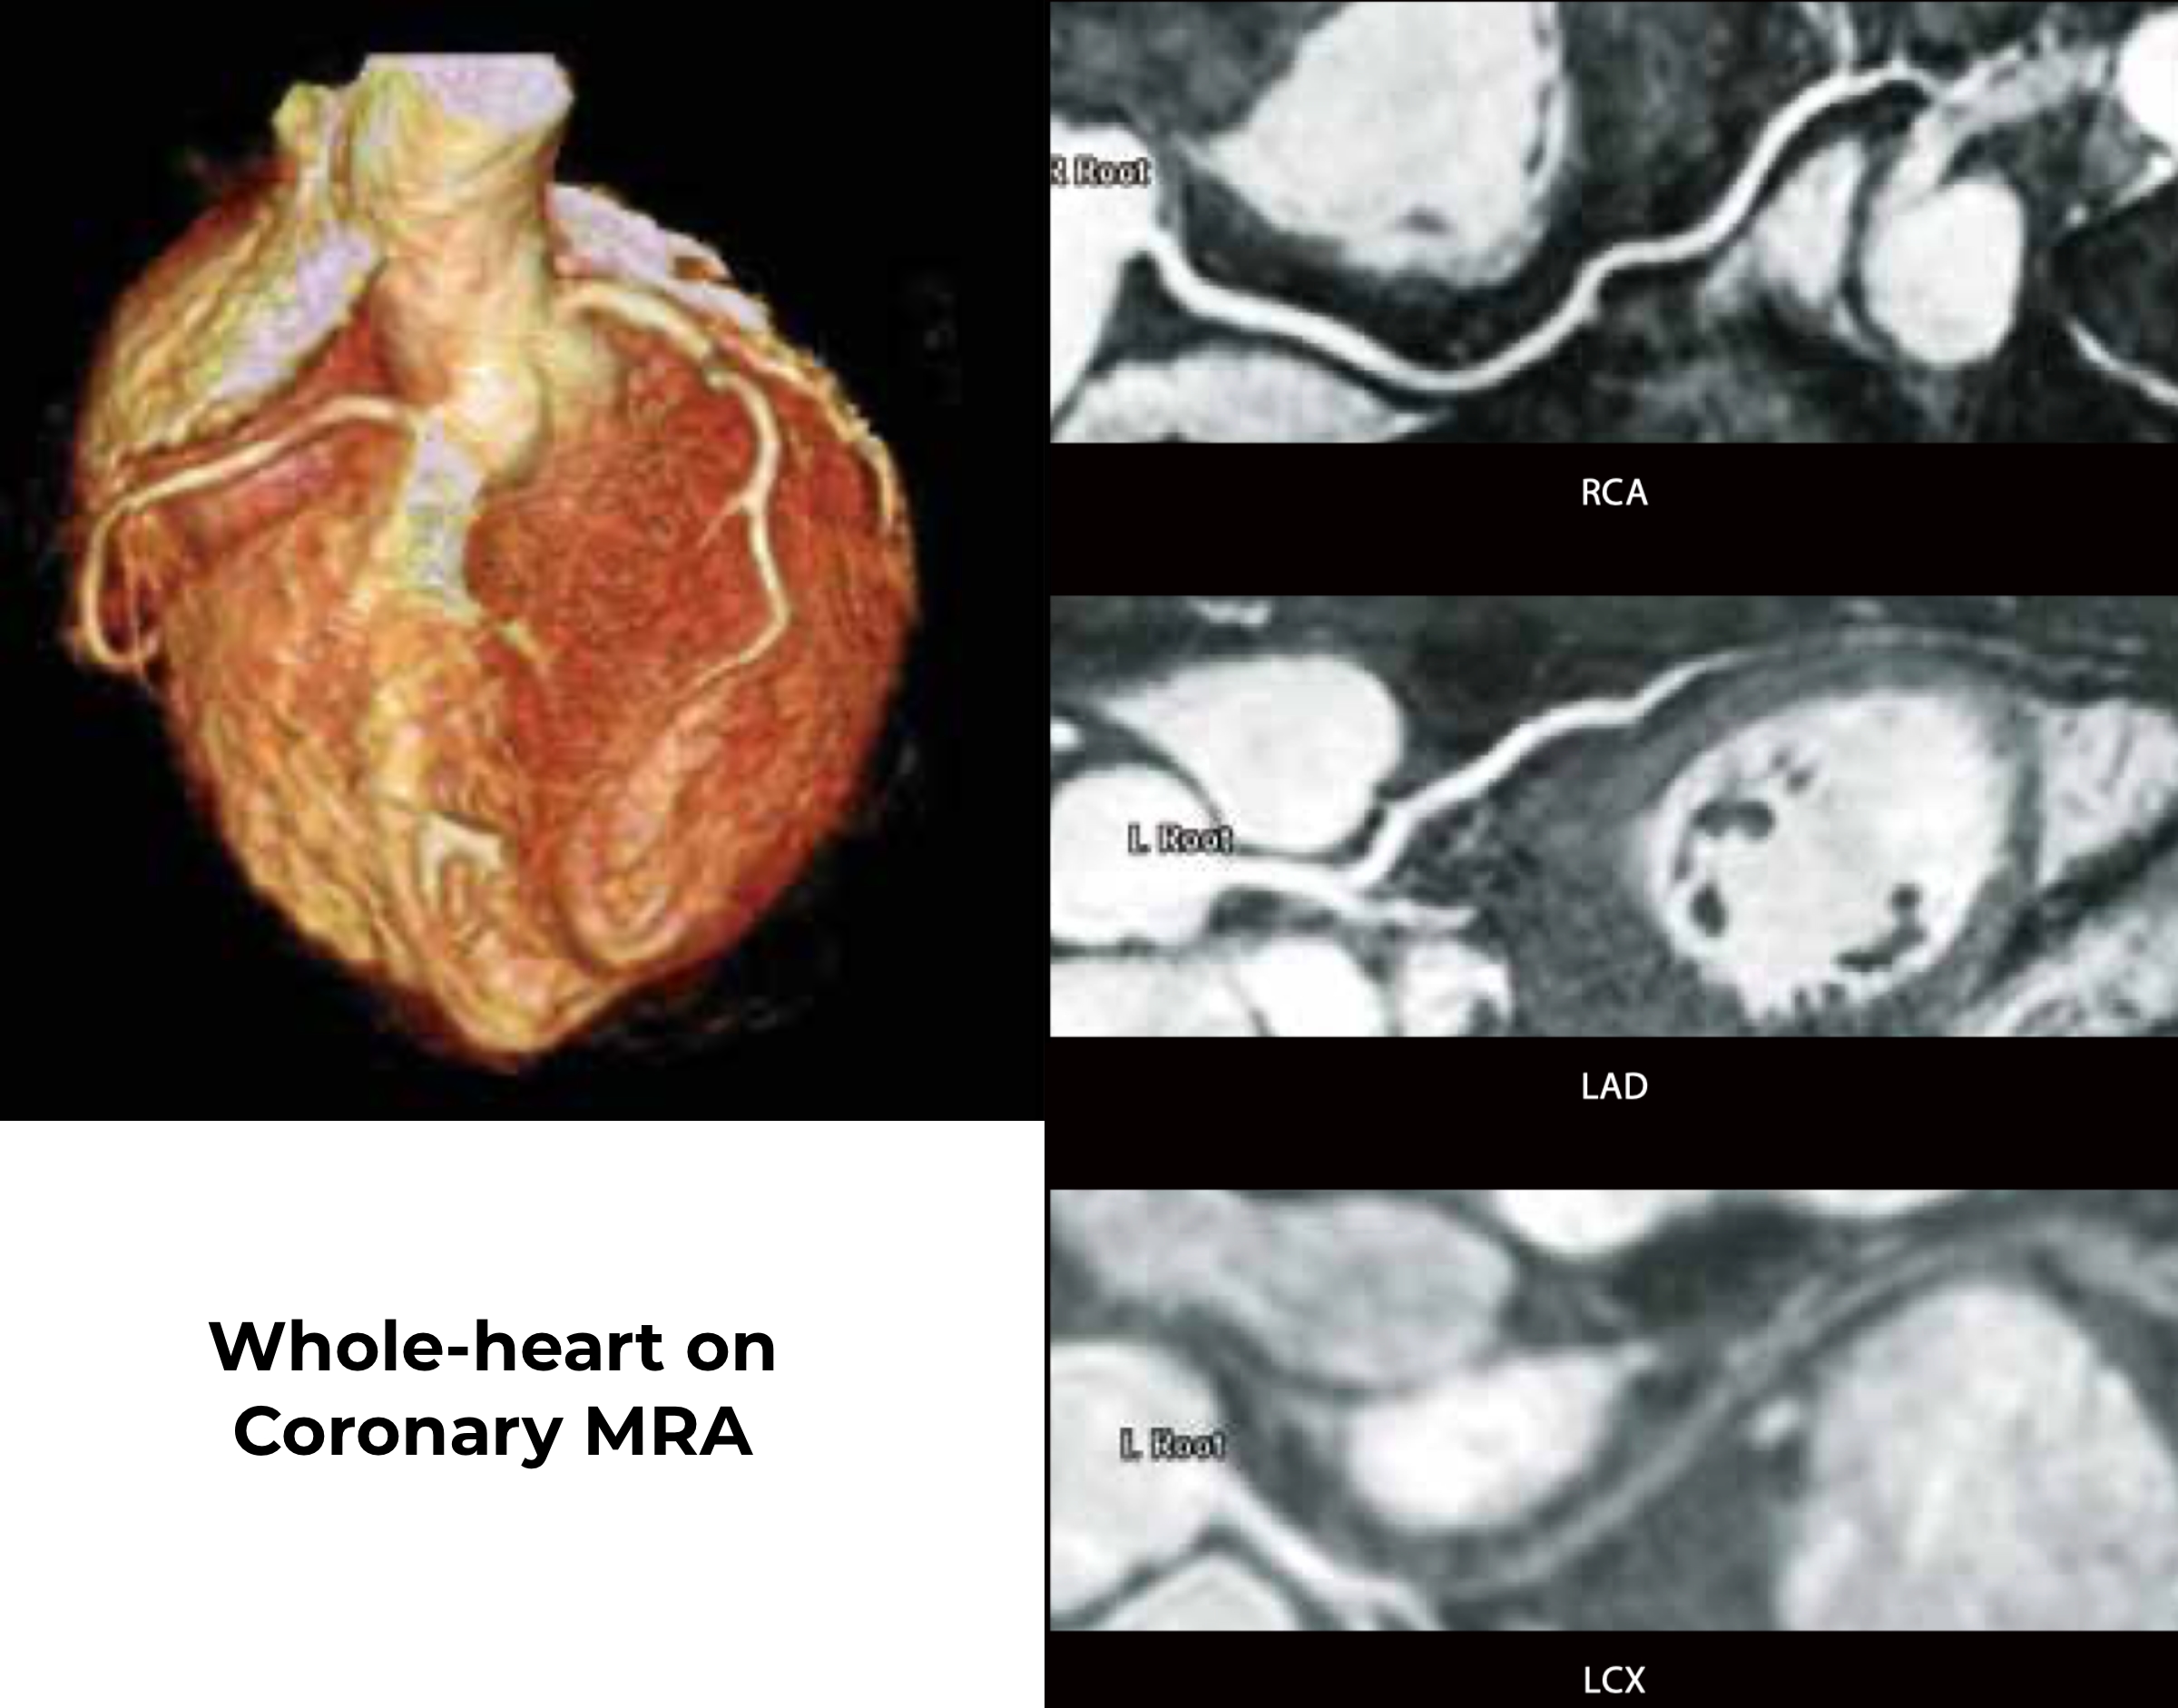

При МР-ангіографії коронарних артерій не було виявлено значного стенозу. Зниження сигналу спостерігалося в дистальному сегменті лівої передньої низхідної артерії через міокардіальний міст, який часто спостерігався при ГКМП.

Якість зображення трохи погіршилася через часте передчасне скорочення шлуночків, але все одно піддавалося діагностиці. На МРА коронарних артерій немає значного стенозу.

Коронарна МРА важлива для виключення ішемічної хвороби серця у пацієнтів із саркоїдозом, оскільки 50% пацієнтів мають аналогічну картину пізнього посилення гадолінію із ішемічною хворобою серця.